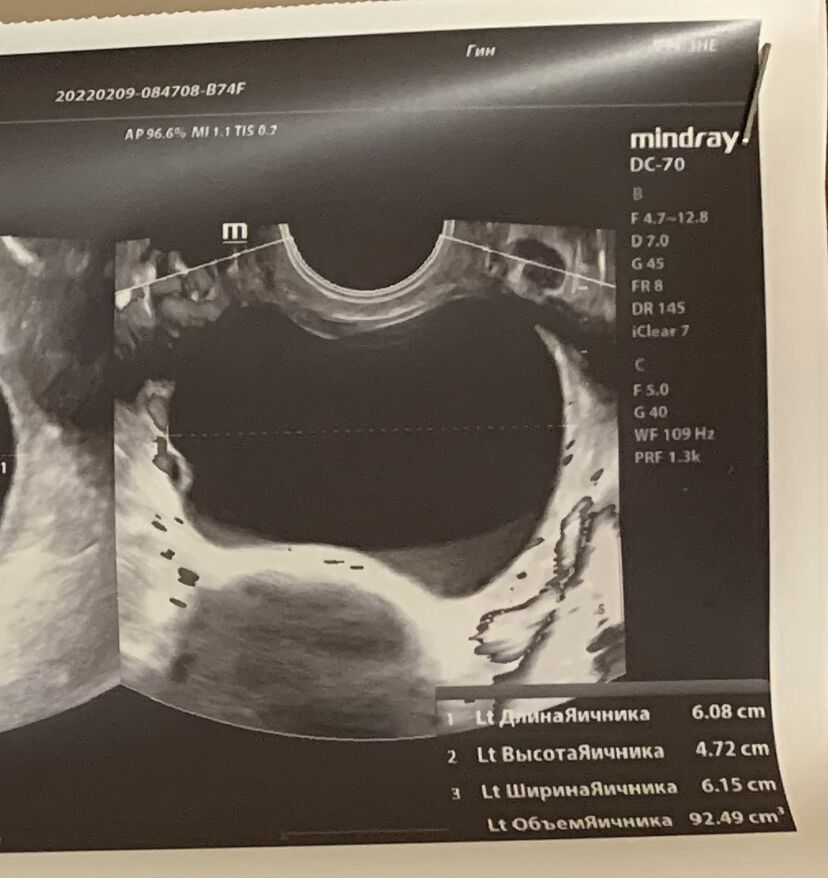

В мл 92.5

А в сантиметрах мне не понятно

Как это непонятно? Там размеры 3*2*4 , это трехмерный размер.

Было 81, стало 92,5

Я так понимаю у меня 92.5 мм, тоесть почти 10 см

Значить нужно операцию

Вы читать умеете? Это размеры яичника 6*4*6 см

Ну там же русским языком написано, что это объем яичника.